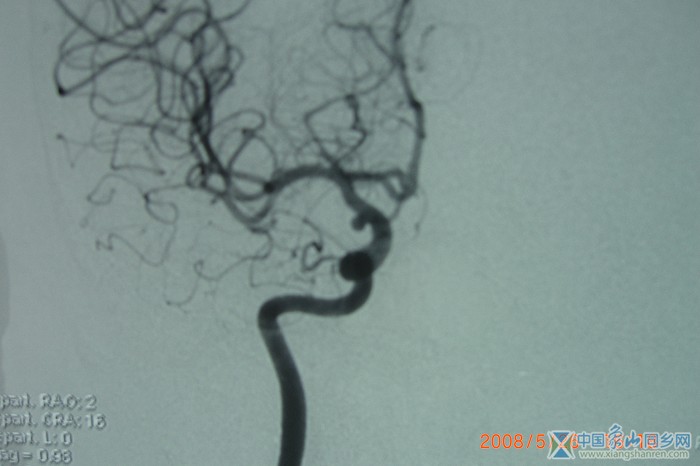

经股动脉插管全脑血管造影,这就是人脑的血管

这就是人脑的血管.考试  请问石医生,动脉瘤在那个部位?.

动脉瘤血管造影_(1).JPG

的确是这样的,象此类病人首先就是介入治疗,而且这个动脉瘤位置好.但是,这个病人经济状况比较差,我定于周六上午给她做动脉瘤夹闭术.